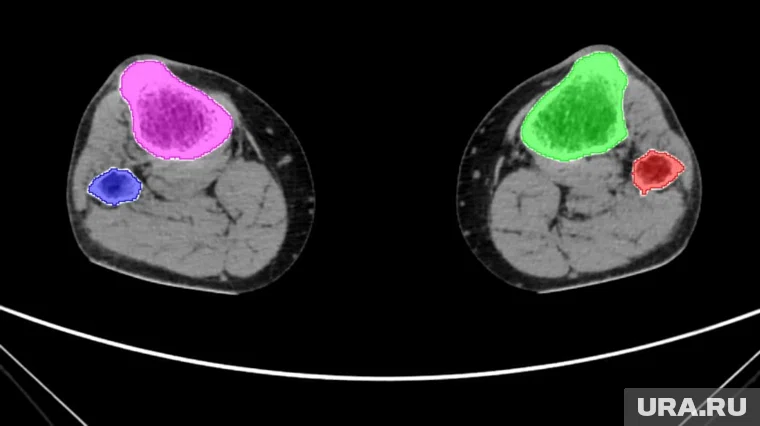

Разработка направлена на решение задач замещения костей после серьезных травм, врожденных дефектов или онкологических заболеваний. В подобных случаях требуется точное воспроизведение геометрии кости для создания имплантата. В КГУ пояснили, что для обучения нейросети ученые в полуручном режиме обработали около 5 тысяч снимков компьютерной томографии, вручную выделяя костные фрагменты на каждом изображении. Благодаря этому алгоритм научился с 98% точностью определять костную ткань на новых томографических срезах менее чем за минуту.

Благодаря внедрению искусственного интеллекта специалисты могут оперативно создавать трехмерные модели костей пациента, что ускоряет процесс подготовки к операции и повышает качество лечения. На основе результатов сегментации врач визуально определяет границы имплантата, а специализированное программное обеспечение формирует 3D-модель изделия. В университете отмечают, что следующая задача — разработка комплексной платформы, которая объединит автоматическую сегментацию КТ-снимков, поиск патологий и построение моделей имплантатов.